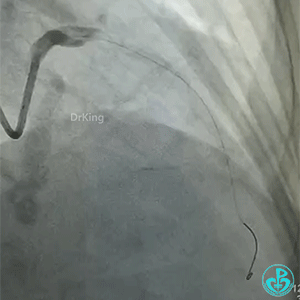

导丝怎么扩真怪!急性心梗前降支导丝通过顺利,球囊扩张后导丝移位很多!不在原来的血管腔!_https://www.jmylbn.com_新闻资讯_第4张

前降支也后扩了。